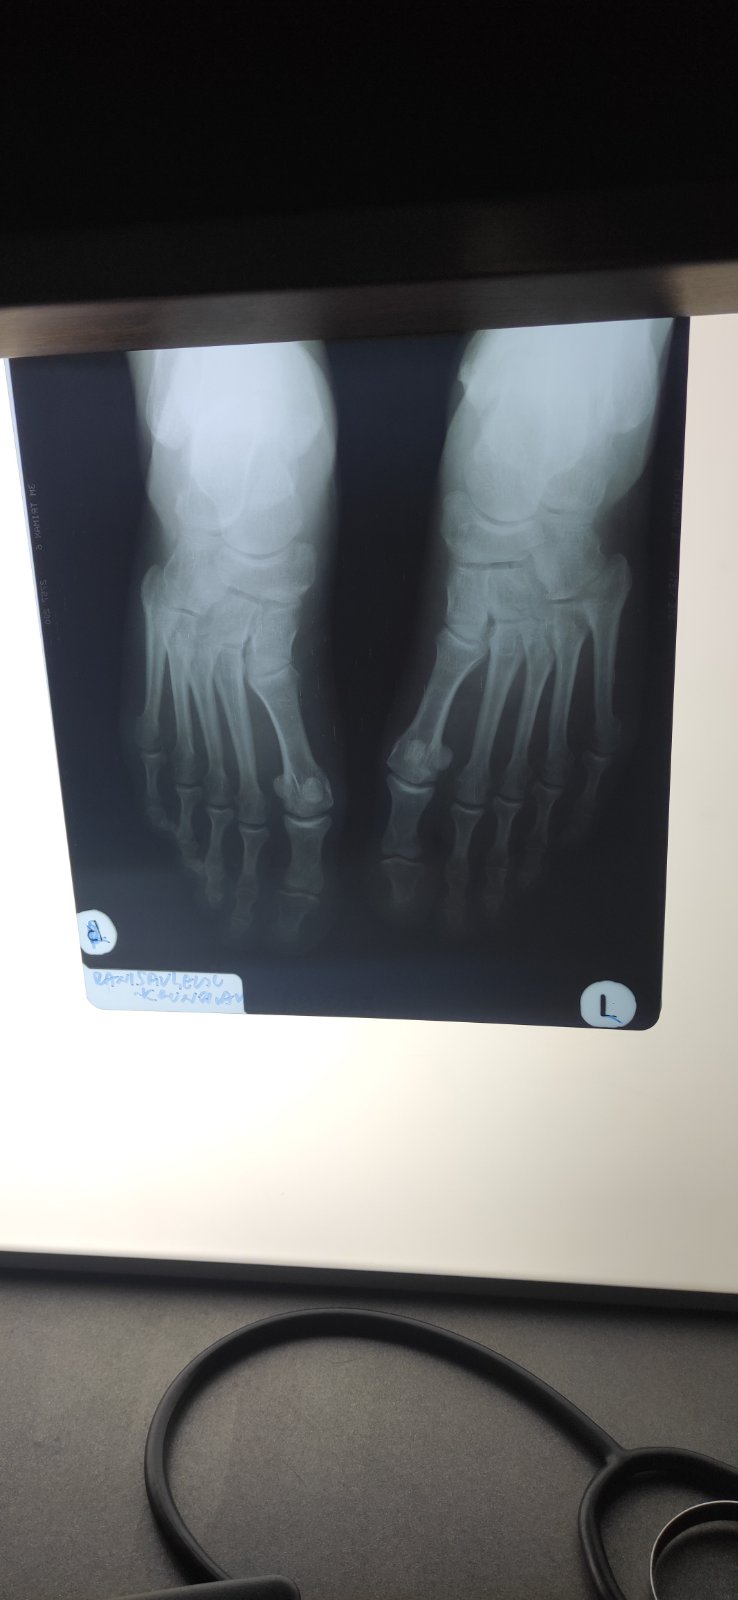

Dijagnostika: Reumatolozi koriste različite dijagnostičke metode kako bi identifikovali i potvrdili različite reumatske bolesti. To uključuje fizički pregled, laboratorijske analize, rendgenske snimke, magnetsku rezonancu (MRI), ultrazvuk i druge dijagnostičke metode.